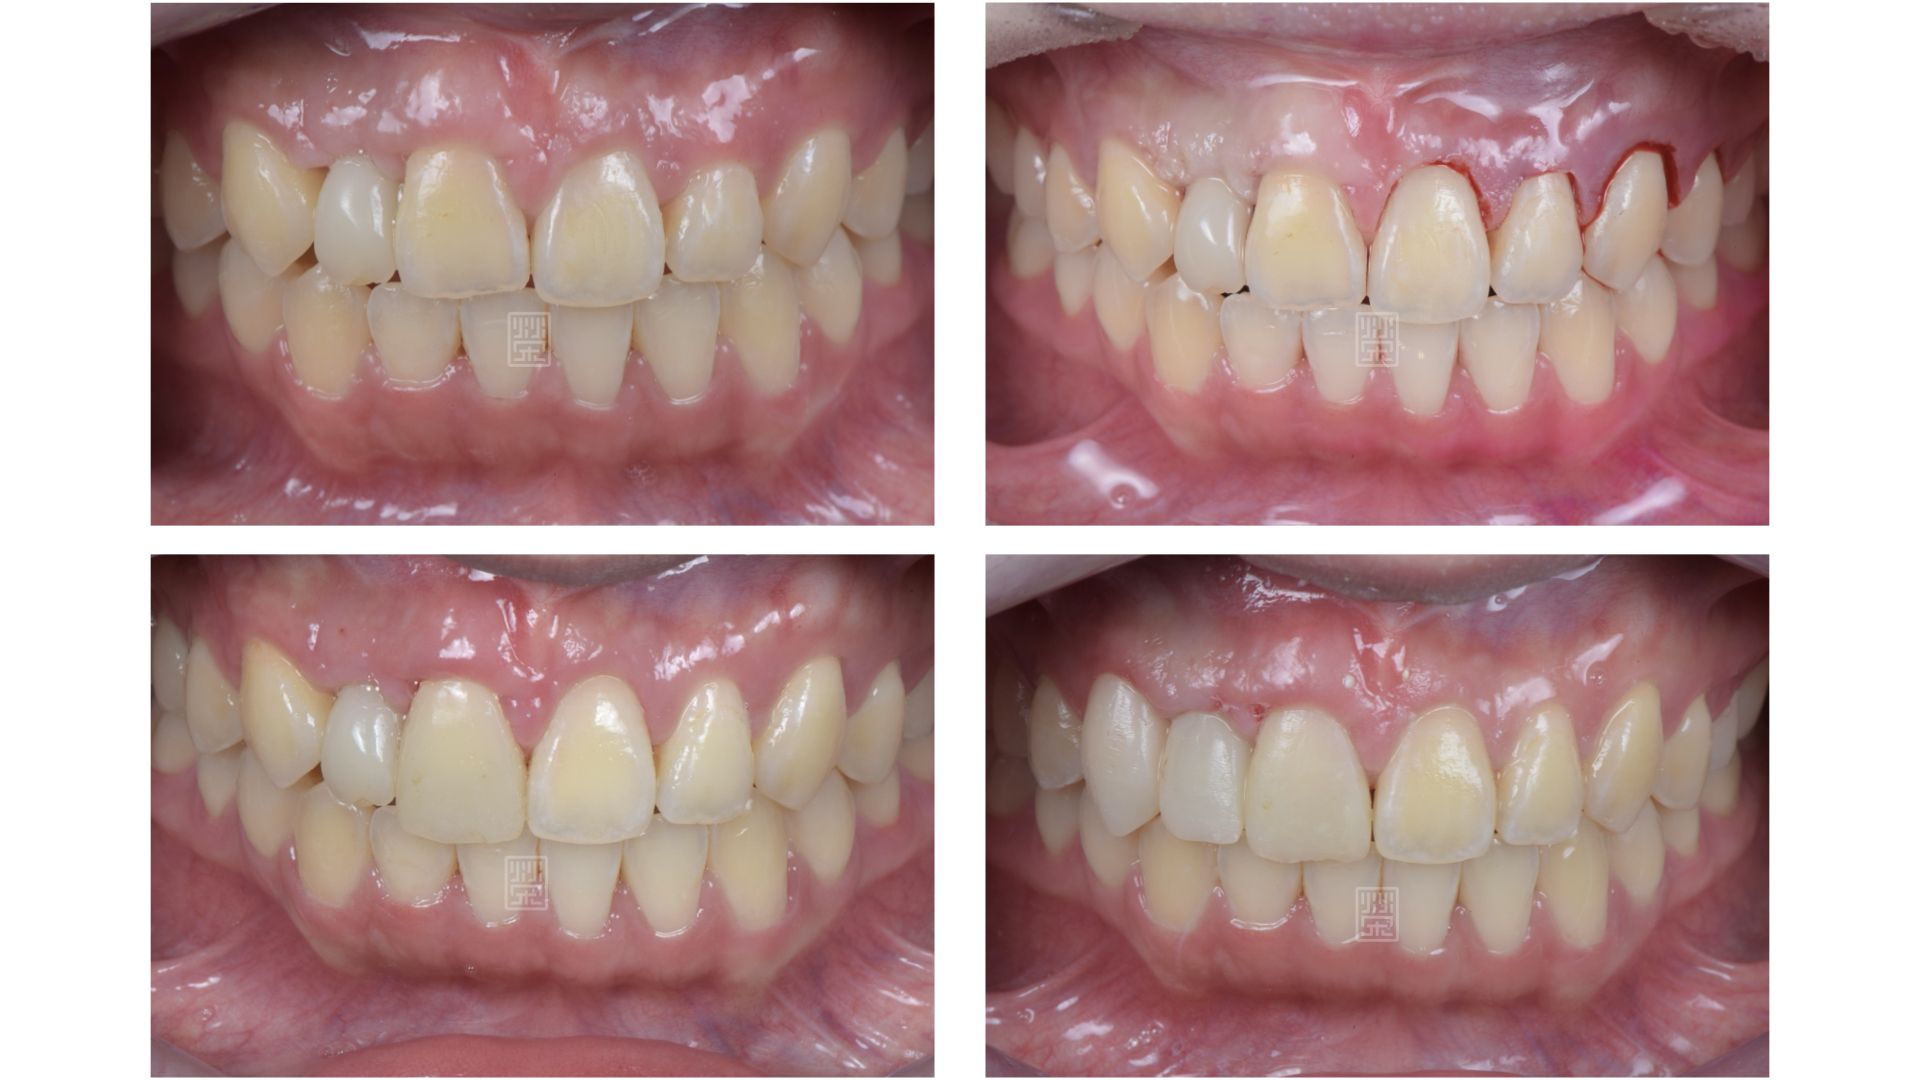

治療前牙齒因車禍有縫且缺牙

矯正移出側門牙空間

長期缺牙側門牙空間不足